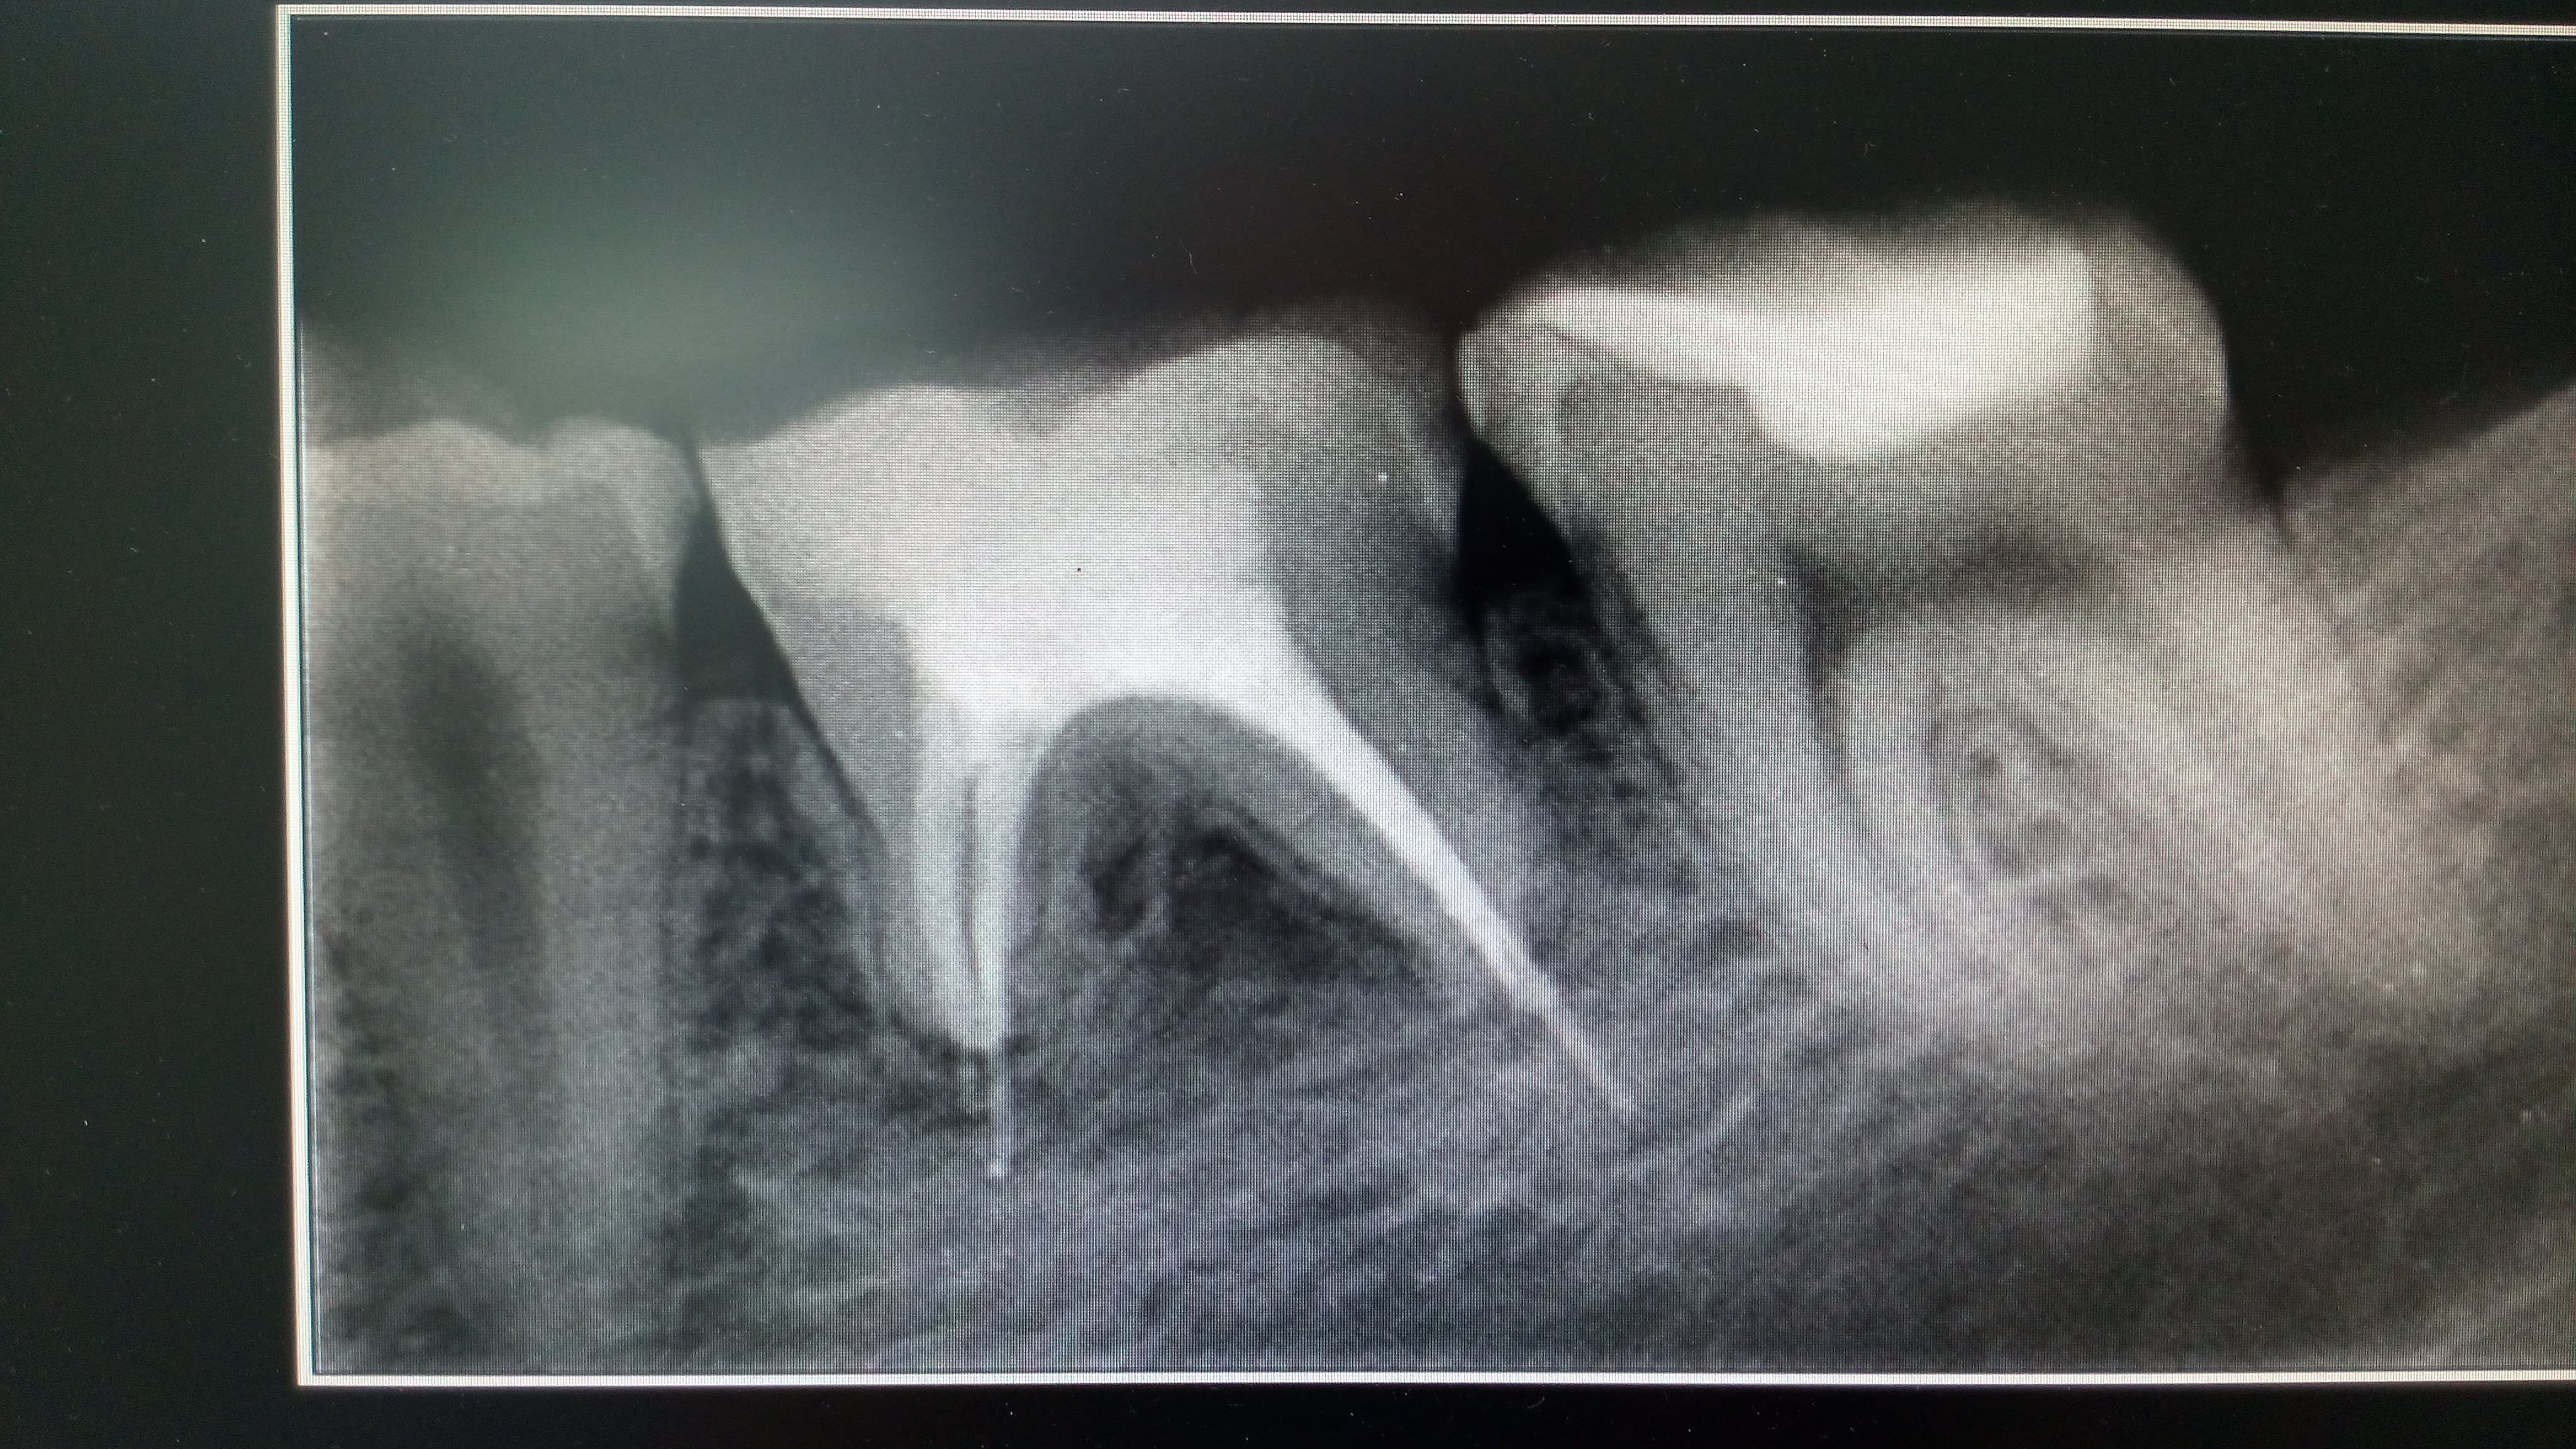

Je souhaiterais avoir vos avis concernant la prise en charge de cette dent. Une endo a été faite, mais seuls les canaux mésiaux ont été obturés.

L'apex de racine distale a été totalement grignoté par l'abcès . J'ai drainé et mis le patient sous AB.

Comment obturer la racine D? Que feriez-vous?

Endo cone moulé et surement résection apicale dans la foulée. Ou obturation titane.

Ca risque d'être tendu la biodentine dans un canal... Obture plutot au cone + bioroot si tu n'as pas l'expérience du truc,, même en faisant un dépassement aucun problème vu que tu fais la résection apicale/curetage après.